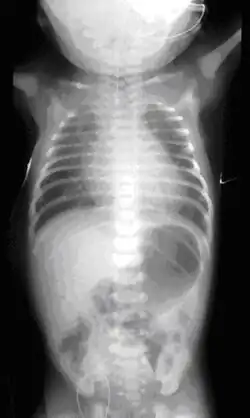

On plain X-ray, a feeding tube will not be seen pass through the esophagus and remain coiled in the upper oesophageal pouch.[11]

If any of the above signs/symptoms are noticed, a catheter is gently passed into the esophagus to check for resistance. If resistance is noted, other studies will be done to confirm the diagnosis. A catheter can be inserted and will show up as white on a regular x-ray film to demonstrate the blind pouch ending. Sometimes a small amount of barium (chalk-like liquid) is placed through the mouth to diagnose the problems. However, performing such an oral contrast study is not advised due to a risk of aspiration.[30]